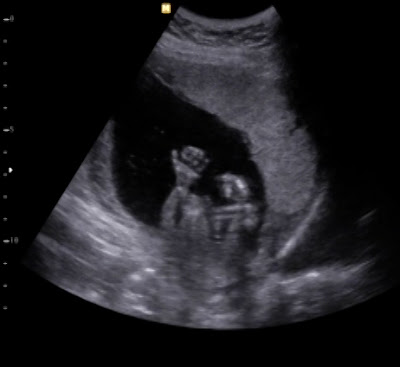

11 weeks and 4 days

This ultrasound was scheduled only four short weeks after the first one, but look at the difference! While the baby still looked like a bean before, it's actually a tiny little human right now!